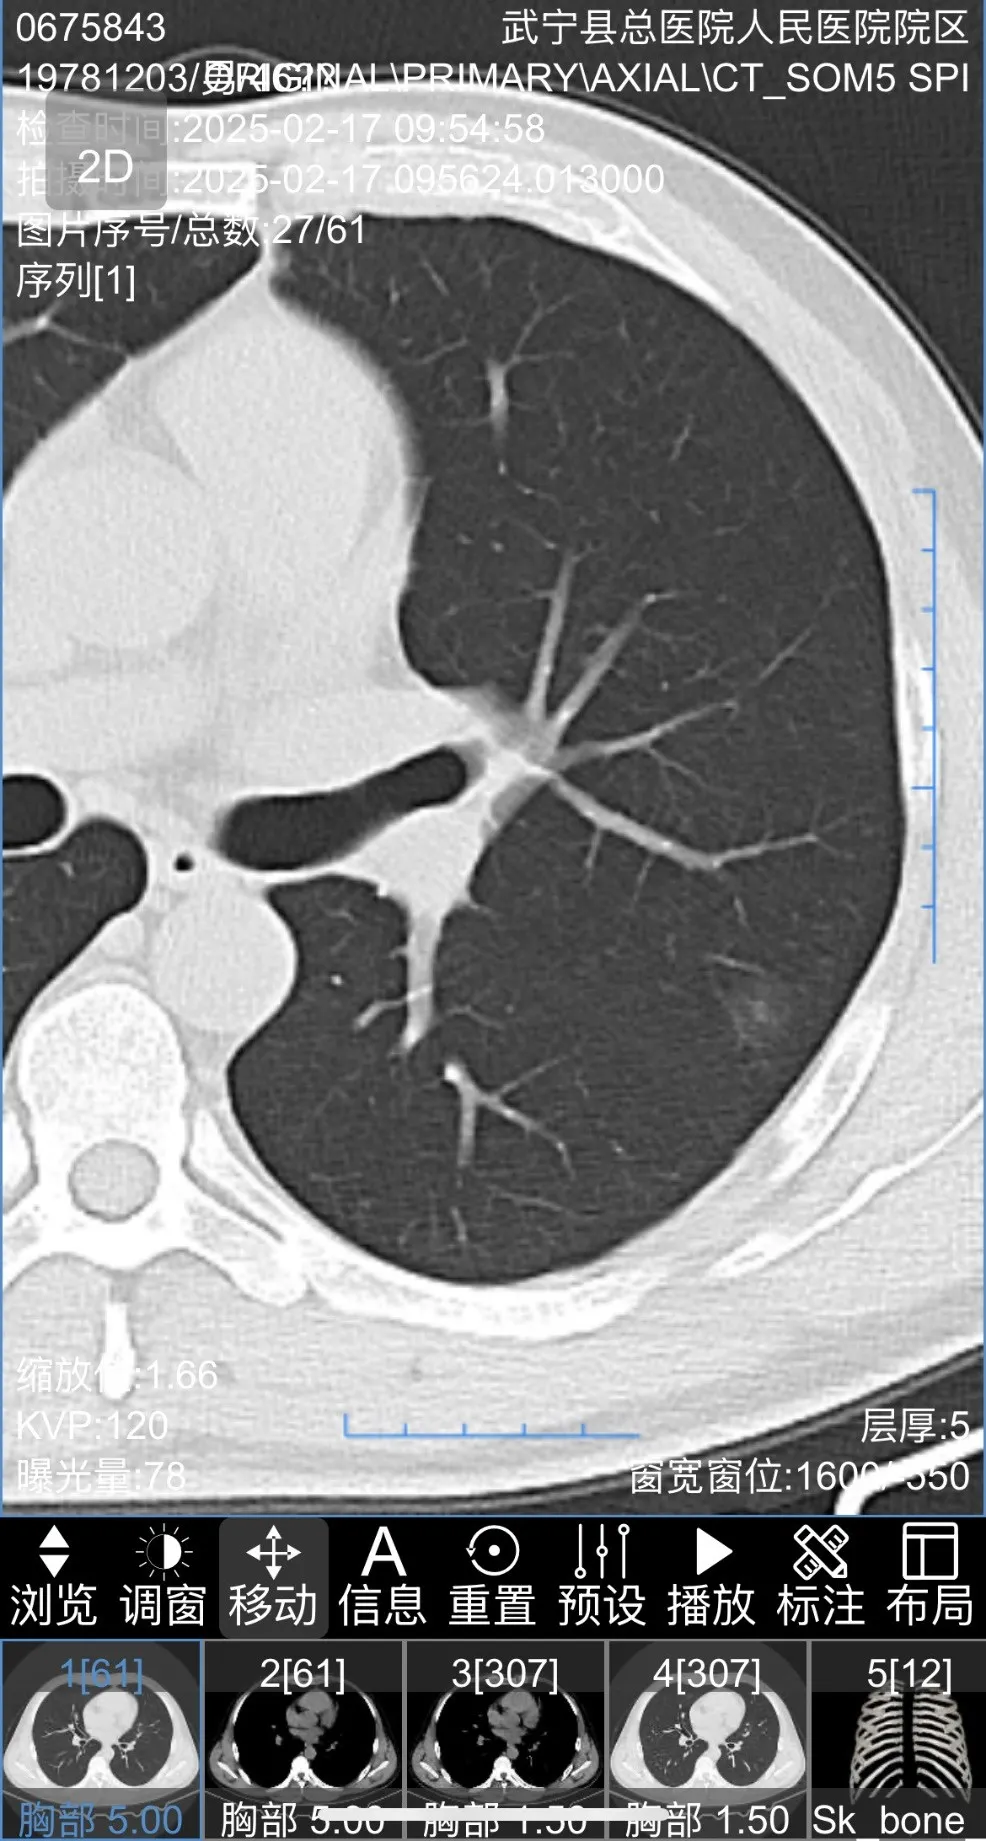

患者胸部(bù)CT圖片如下

三維重建後圖片如下

最終為患者行左肺上葉S1+2c與S4a聯合亞段切除及S1+2a段(duàn)楔形切除術。患者術後2天出院,恢(huī)複良好,手術後對肺功能無影(yǐng)響。結節1病理為(wéi)原位癌,結(jié)節2為良好病灶。患者對91麻豆视频(men)手術方(fāng)案非(fēi)常滿意,痊(quán)愈出院。

三維重建輔助下肺癌精準肺段切除術,是一種先進的肺癌手術方式。主要(yào)借助CT影(yǐng)像數據,利(lì)用計(jì)算機技術對肺部、血管及支氣管等進行三維(wéi)立(lì)體建模,清晰呈現肺部解剖結構。優勢在於,醫生能精準定位腫瘤位置和(hé)邊界,規劃手(shǒu)術路徑,準確切除包含腫瘤的肺段,保留更多健康肺組織(zhī),提升患者(zhě)術後(hòu)肺功能和生活質量。同時減少術中出血(xuè)、降低損傷周圍組織風險。